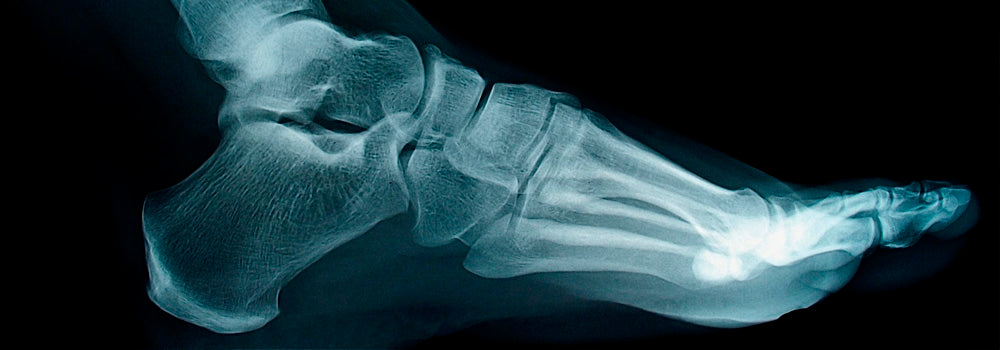

Проверяйте ноги вашего ребенка на регулярной основе, поскольку маловероятно, что он скажет вам сразу, если будет чувствовать боль. Вот некоторые общие проблемы наиболее часто встречающихся у детей ног: Вросшие ногти на ногах Такое явление происходит, когда ногти врастают в окружающую плоть. Если ваш малыш имеет один вросший ноготь, это может привести к покраснению кожи на пальцевые ноги, опухлости и боли. Внимательно следите, как вы подстригаете ногти малыша, чтобы помешать их врастанию. Используйте кусачки для ногтей. необходимо. Никогда не отрезайте бока ногтей на ногах вашего ребенка и не делайте их слишком короткими. Уголки ногтей должны находиться подальше от мясистой части ног. Плоскостопие Плоскостопость является нормальной для детей раннего возраста. Частично это происходит из-за осанки, а отчасти потому, что детские ноги имеют больше жира, чем взрослые. Когда ребенок будет делать свои первые шаги, не забывайте о необходимости использования детской ортопедической обуви . Детская ортопедическая обувь правильно сформирует ножку и обеспечит Вашему малышу комфортом. Косолапость Косолапость – это врожденное состояние, при котором одна или обе ноги согнуты внутрь и вниз. Лечение косолапости начинается вскоре после рождения и обычно включает в себя физиотерапию, чтобы вернуть ноги обратно в правильную форму.

Плоскостопость, или снижение сводов стопы у ребенка требует немедленной реакции родителей. Консультации у врача, специальная гимнастика и правильная детская ортопедическая обувь – первые шаги к борьбе с плоскостопием. А чтобы избежать такой проблемы, необходимо устранять или предотвращать возможные причины ее появления (разумеется, при исключении врожденного плоскостопия). Поэтому сегодня мы перечисляем основные причины появления плоскостопия у детей: 1. Рахит – недостаточное количество витаминов в организме делает мышцы слабыми, неспособными хорошо удерживать вес тела. 2. Лишний вес – основная причина статического плоскостопия. Стопа также не выдерживает слишком большой нагрузки и уплотняется. 3. Перенесенные травмы и переломы – вот причина травматического плоскостопия. Следите за тем, чтобы Ваш ребенок играл в безопасном месте, особенно это касается игр на улице с друзьями. 4. Неправильная обувь может не только доставить ребенку неудобства, но и навредить, провоцируя возникновение плоскостопия. Большинству родителей известно, что лучшим выбором для ребенка станет детская ортопедическая обувь. Дело в том, что такие изделия работают не только как лечебные, но и как профилактические, поэтому способны помешать развитию плоскостопия. В холодное время родителей также порадует зимнюю детскую ортопедическую обувь . Подошва с зимним протектором будет обеспечивать хорошее сцепление со скользкими поверхностями, чтобы помогать ребенку избегать травм. Жесткий задник, теплый мех, закругленный носок и отражатели для ночного периода понравятся и Вам и Вашему ребенку. Такую качественную ортопедическую обувь можно купить в нашем интернет магазине. Давайте выбирать для своих малышей самые лучшие продукты.

От правильного формирования детских стоп зависит будущее человека, а именно: его походка, возникновение или отсутствие заболеваний, осанка. Эти вещи оказывают огромное влияние на весь организм, поэтому подобные вопросы не стоит обходить стороной. К сожалению, в последнее время жалобы на появление дефектов и заболеваний детских ножек только увеличиваются. Почему это происходит? Какие причины возникновения дефектов наиболее распространены? Как с ними справиться? Сегодня мы постараемся ответить на все эти вопросы. В большинстве случаев проблемные стопы у ребенка формируются из-за нарушения мышечного тонуса (особенно когда пальцы малыша постоянно находятся в сжатом положении), в результате которого возникают такие проблемы как плоскостопие, косолапость и другие дефекты. Плоскостопость – это одно из самых распространенных нарушений развития детских ног. При этом предпосылок к появлению данного дефекта множество: перенесенные травмы, рахит, слабые мышцы, неправильная детская обувь. Плоскостопость также может быть врожденным явлением. С момента рождения у ребенка плоская стопа это абсолютно нормально. Впоследствии она начинает убирать правильную форму. Если этого не происходит, следует обратиться к врачу – ортопеду. Только он может определить наличие или отсутствие плоскостопия у малыша. Самый простой способ определить наличие плоскостопия Зарисуйте стопы малыша (для этого можно использовать краски, чернила и т.п. Только смывайте сразу и смотрите, чтобы у ребенка не возникало на это аллергической реакции.) Попросите испытателя встать на чистый лист. Если плоскостопия нет, под сводами стопы не будет отпечатка. Конечно, главный вопрос еще впереди: как избавиться от плоскостопия? Во-первых, обязательны регулярные консультации у специалиста. Во-вторых, правильная детская обувь. Для профилактики и лечения дефектов ног создана детская ортопедическая обувь. Оно и ножку правильно сформирует и от дальнейшего развития проблем защитит. В нашем магазине можно купить детскую ортопедическую обувь от бренда Мемо, уже давно запомнившуюся родителям своим высоким качеством, приятным видом и неутомимой работой специалистов над своими изделиями. Мы же хотим пожелать, чтобы Ваш малыш всегда был доволен состоянием своих ножек и активен во всех своих начинаниях.

Ортопедические стельки – это одно из важнейших средств при борьбе с плоскостопием. Их рекомендуется начинать использовать уже при первой стадии развития плоскостопия. Изделия хорошо корректируют выявленные дефекты в начале развития проблемы, а также предотвращают дальнейшее их развитие. Ортопедические стельки нужно укладывать в обувь как дома, так и на улице в случаях, когда вы испытываете длительную нагрузку на ноги. В нашем интернет магазине можно купить качественные стельки от производителя Kaps, которые представлены в широком ассортименте. В наличии интернет магазина каркасные и бескаркасные ортопедические стельки. Чем эти изделия отличаются друг от друга? Каркасные ортопедические стельки предназначены для лечения плоскостопия первой и второй ступеней. В их составе – активированный уголь, препятствующий неприятному запаху и влажности. Ортопедические стельки изготовлены из натуральной кожи, поэтому ножке они принесут максимальное удобство. Бескаркасные ортопедические стельки хорошо справятся с влажностью. Созданные для использования в случаях комбинированного плоскостопия третьего уровня, ортопедические стельки защищают стопу от возникающих при ходьбе микроударов, а также помогут решить проблему возникновения натоптышей. Дети тоже нередко страдают появлением плоскостопия и других дефектов ног. Для решения проблемы подбора ортопедических стельок посмотрите на нашем сайте детские ортопедические стельки Memo и Kaps. Вместе с правильной обувью они хорошо поддерживают маленькие ножки в правильном положении, облегчают передвижение и способствуют хорошему развитию детских стоп. Помните, что за ножкой малыша нужно смотреть и в случае роста размера ног, естественно, ортопедические стельки нужно поменять. Не стоит забывать о регулярных консультациях у врача – ортопеда